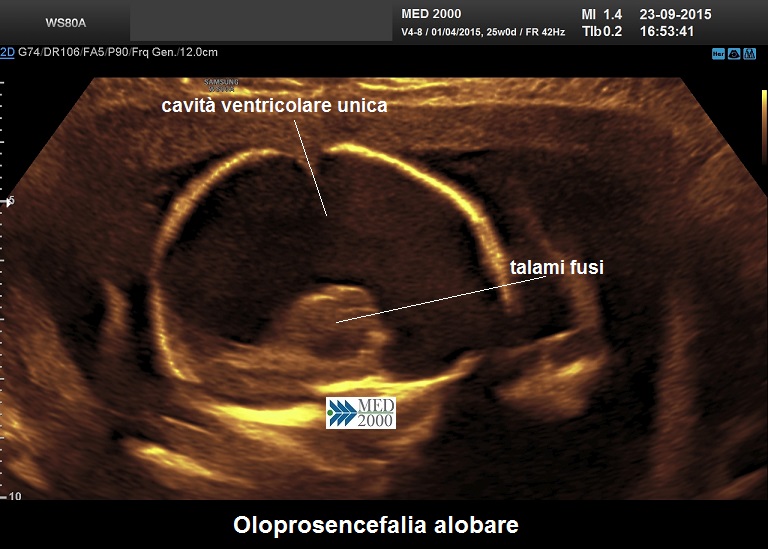

Forma alobare:

1.     ampia cavità ventricolare unica

2.     corteccia cerebrale sottile

3.     scissura interemisferica assente

4.     falce cerebrale assente

5.     setto pellucido assente

6.     3° ventricolo assente

7.     disgenesia del corpo calloso

8.     talami fusi